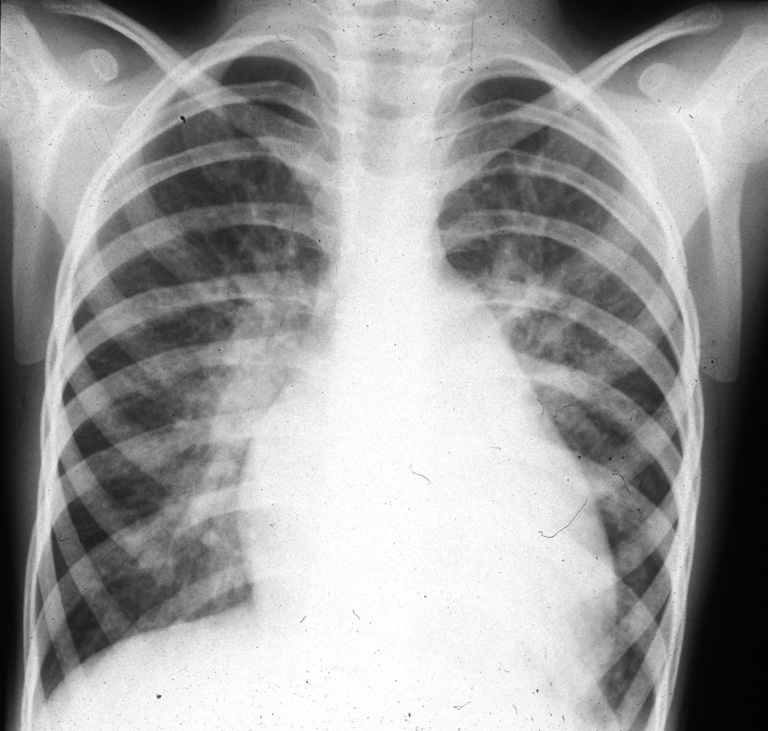

La coarctation préductale (c’est-à-dire située en amont de l’émergence du canal artériel ou ductus arteriosus), ou sténose de l’isthme de l’aorte, est une forme grave de la coarctation aortique, symptomatique dès les premiers jours de vie, mais les symptômes n’apparaissent qu’au moment de la fermeture du canal artériel. La chirurgie est urgente (figures 1 et 2).